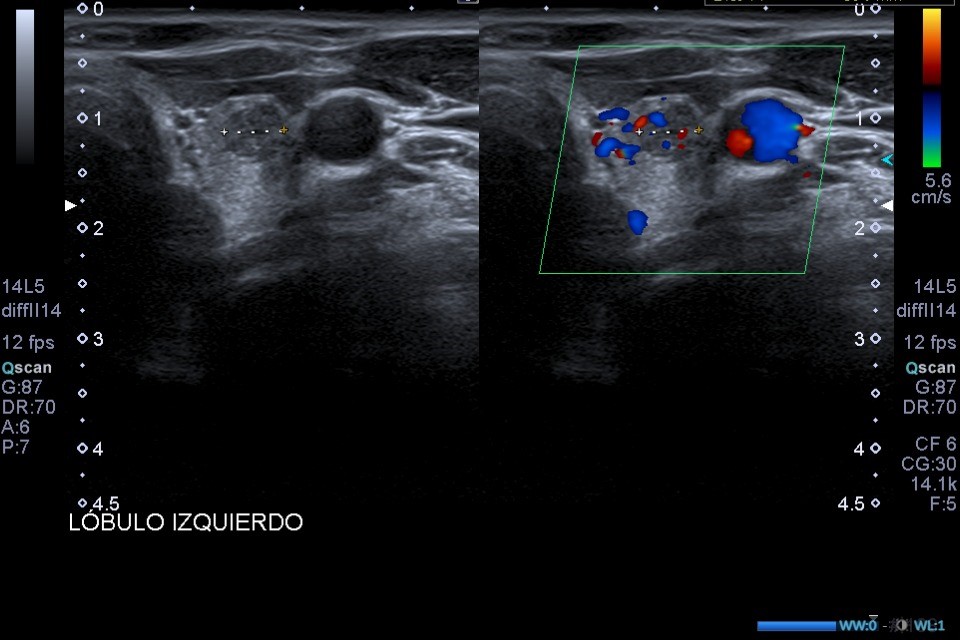

Ecografía de tiroides en consulta: En el LTI presenta dos lesiones nodulares en el área central del lóbulo tiroideo, presentando ambas un aspecto heterogéneo, bordes y márgenes mal definidos y microcalcificaciones.

Dada la presencia de nódulos tiroides con patrones ecográficos de alta sospecha de malignidad (bordes y márgenes mal definidos y presencia de microcalcificaciones), se solicita ecografía tiroidea reglada, y derivar a especialista en función de resultados.